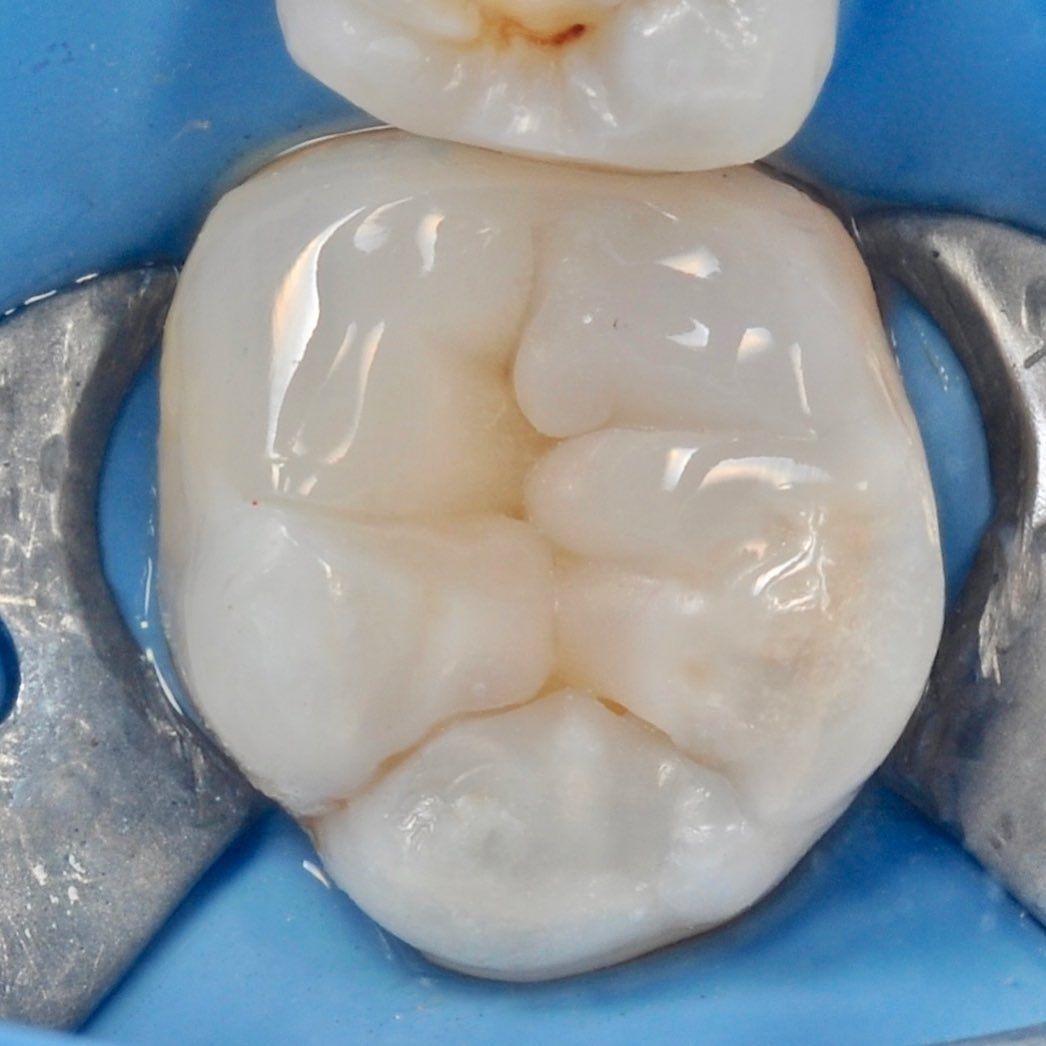

зуб с обработанными каналами

Лечения пульпита

Каналы наших зубов можно представить как дерево имеющее множество ответвлений. Задача врача провести их обработку сохранив ткани зуба.